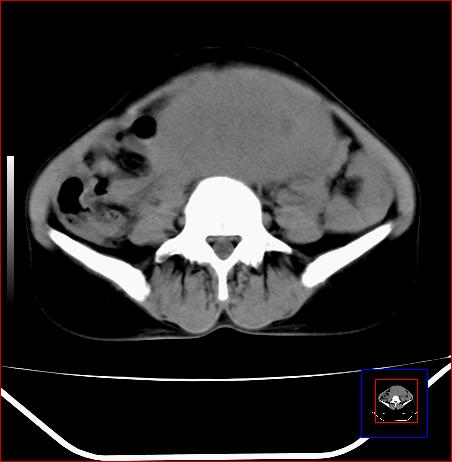

标题: CT15141:子宫肌瘤还是卵巢肿瘤 [打印本页]

标题: CT15141:子宫肌瘤还是卵巢肿瘤

腹部包块1年余,近两月明显增大,月经量多

病灶呈实性包块,边界清晰,似与子宫分界不清,考虑:子宫肌瘤

子宫体积增大,内密度不均匀。边缘清晰。考虑子宫肌瘤。

病灶呈实性包块,边界清晰,似与子宫分界不清,考虑:子宫肌瘤可能性大。其他待排

子宫体积增大,内密度不均匀。边缘清晰。考虑子宫肌瘤可能性大。